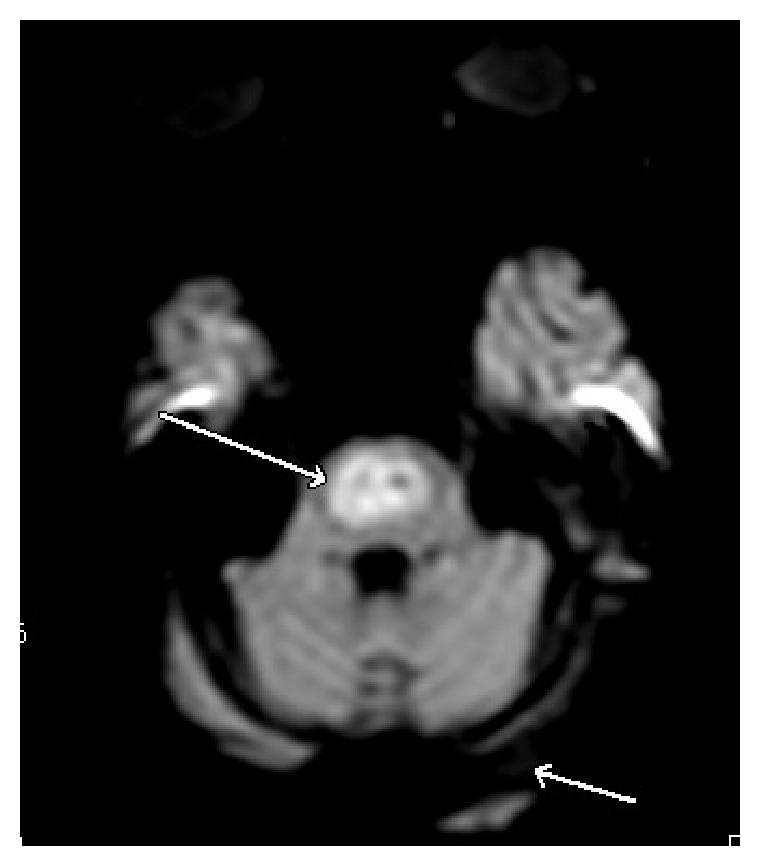

Central pontine myelinolysis (CPM), a potentially fatal and debilitating neurological condition, was first described in 1959 in a study on alcoholic and malnourished patients. It is a condition most frequently related to rapid correction of hyponatremia. Chronic alcoholism associated CPM tends to be benign with a favorable prognosis compared to CPM secondary to rapid correction of hyponatremia. We describe a normonatremic, alcoholic patient who presented with CPM after a rapid rise in his sodium levels. Our case illustrates the fact that CPM can manifest even in patients who are normonatremic at baseline. Rapid rises in sodium levels should be promptly reversed before clinical symptoms manifest in patient with risk factors for CPM irrespective of their baseline sodium levels. Furthermore, clinical evolution of CPM can be difficult to discern from the natural course of alcohol withdrawal delirium, requiring astuteness and maintenance of a high degree of clinical suspicion on the part of the physician.

桥脑中央髓鞘溶解症(CPM)是一种潜在致命且使人衰弱的神经系统疾病,于1959年在一项针对酗酒和营养不良患者的研究中首次被描述。它是一种最常与低钠血症快速纠正相关的疾病。与因低钠血症快速纠正继发的CPM相比,慢性酒精中毒相关的CPM往往预后良好,较为良性。我们描述了一名血钠正常的酗酒患者,其血钠水平快速上升后出现了CPM。我们的病例说明了即使是基线血钠正常的患者也可能出现CPM这一事实。对于有CPM危险因素的患者,无论其基线血钠水平如何,在临床症状出现之前,应迅速逆转血钠水平的快速上升。此外,CPM的临床进展可能难以与酒精戒断谵妄的自然病程相区分,这需要医生保持敏锐并高度临床怀疑。